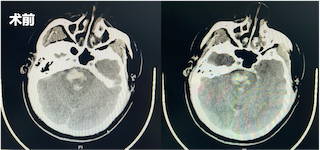

2月16日晚上9时许,47岁的姜某因突发意识丧失伴四肢抽搐送至中南大学湘雅三医院神经内科急诊抢救室。经头部CT检查发现患者脑为干出血。医院神经内科袁毅主任医师、李小波副主任医师、陈益伟主治医师及谢笃杰主治医生等医护人员组成的神经介入团队立即处置,经体表激光立体定向下脑干血肿穿刺清除术,患者转危为安,并于3月18日顺利出院。

据了解,患者送至医院时已经神志昏迷,呼之不应,任凭家属和医生如何呼唤他均没有任何应答与动作。神经内科急诊医生紧急予以完善头部CT,发现患者脑干出血。脑干出血是所有脑出血中最为凶险的类型,预后极差,此时任何的拖延与迟疑均可能将患者推向悬崖边缘。神经内科急诊医生立即与患者家属交代目前病情,紧急与家属沟通并取得同意后,立即邀请神经介入亚专科团队进行抢救。